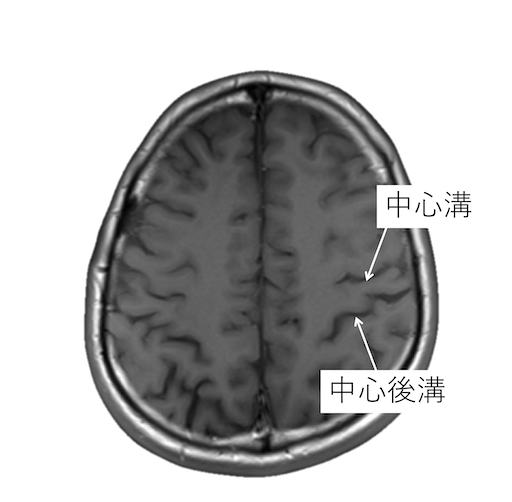

中心溝、中心前溝、中心後溝、中心前回、中心後回のMRI画像における解剖

主に脳梗塞診断などで重要な中心溝、中心前溝、中心後溝、中心前回、中心後回のMRI画像における解剖(CTでも使えます。)をご覧いただけます。

中心溝を同定する際には、以下の4つの原則があります。

・中心前溝は上前頭溝と、中心後溝は頭頂間溝と、連続するが、中心溝が連続する脳溝はない。

・中心後溝の内側端はY字型になり、帯状溝縁部(ちょび髭)は分岐に挟まれる。中心溝の内側端は帯状溝縁部(ちょび髭)のすぐ前にくる。

・脳回の前後幅は中心前回が後回より太い。

・中心前回の手指運動野は後方凸を示す(precentralknob sign)